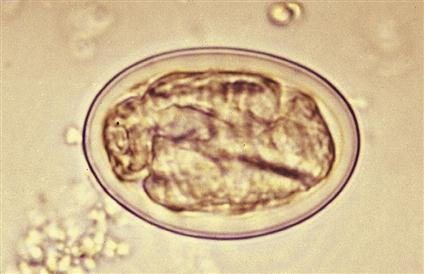

Physaloptera spp.

Host: canines and felines; Location: lumen of the stomach or small intestine; Common name: stomach worm, Diagnosis: fecal flotation and vomits